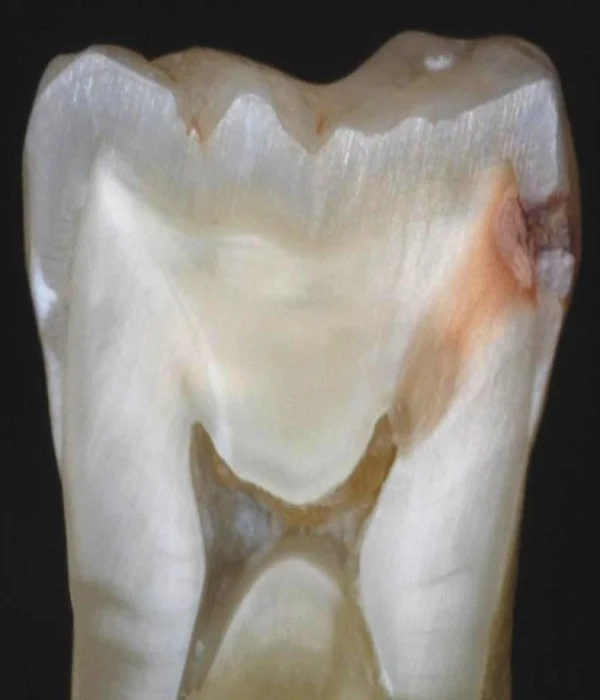

La caries es un proceso bacteriano, crónico, que provoca la destrucción de los tejidos calcificados de los dientes: el esmalte, la dentina y el cemento que la recubre.

- Caries en esmalte con lesión cavitada, o lo que es lo mismo, la aparición del primer punto negro o hueco.

- Caries en la dentina. Etapa avanzada en la que la caries ha traspasado el esmalte y ha alcanzado la dentina, comprometiendo áreas más grandes del diente.

La enfermedad consiste en una desmineralización progresiva del diente, que se manifiesta mediante una mancha blanca, diferente al color del esmalte. Esa mancha blanca indica que el biofilm, la película que protege al diente, se ha desgastado, dejando el esmalte expuesto a un medio hostil como el de la boca. Hostil por las bacterias presentes, su PH y la alteración del entorno que hace posible que los ácidos lo penetren.

Muchas veces, la parte visible de una caries es solo la entrada y no muestra su alcance o sus dimensiones reales. Lo cierto es que la cavidad de una caries se agranda diente adentro, y puede comprometer la estructura del diente.